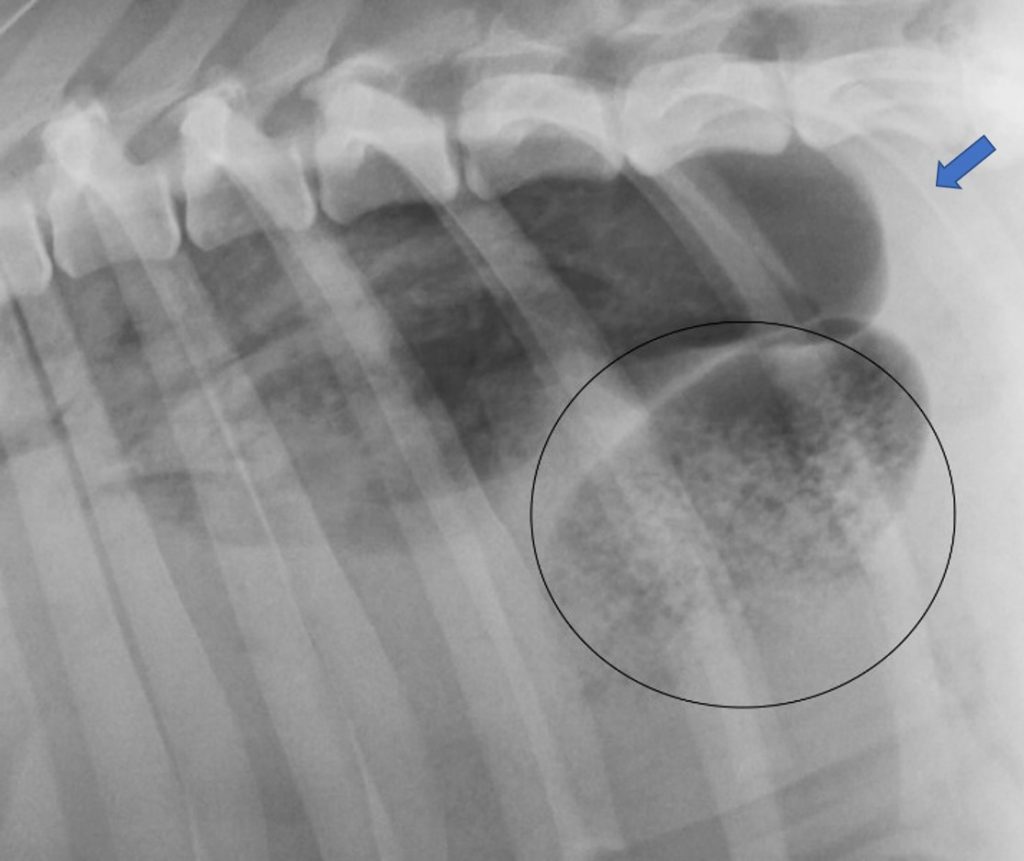

La consolidación pulmonar (fechas) es un signo que aparece en estos casos, pero también en casos de neumonía grave, neoplasia infiltrativa, hemorragia o tromboembolismo pulmonar.

En un estadio temprano el lóbulo afectado tiene mayor tamaño y con márgenes redondeados por la congestión pasiva que sufre al colapsarse inicialmente la vena pulmonar. En una fase más avanzada el volumen del lóbulo pulmonar disminuye por la necrosis del lóbulo afectado.